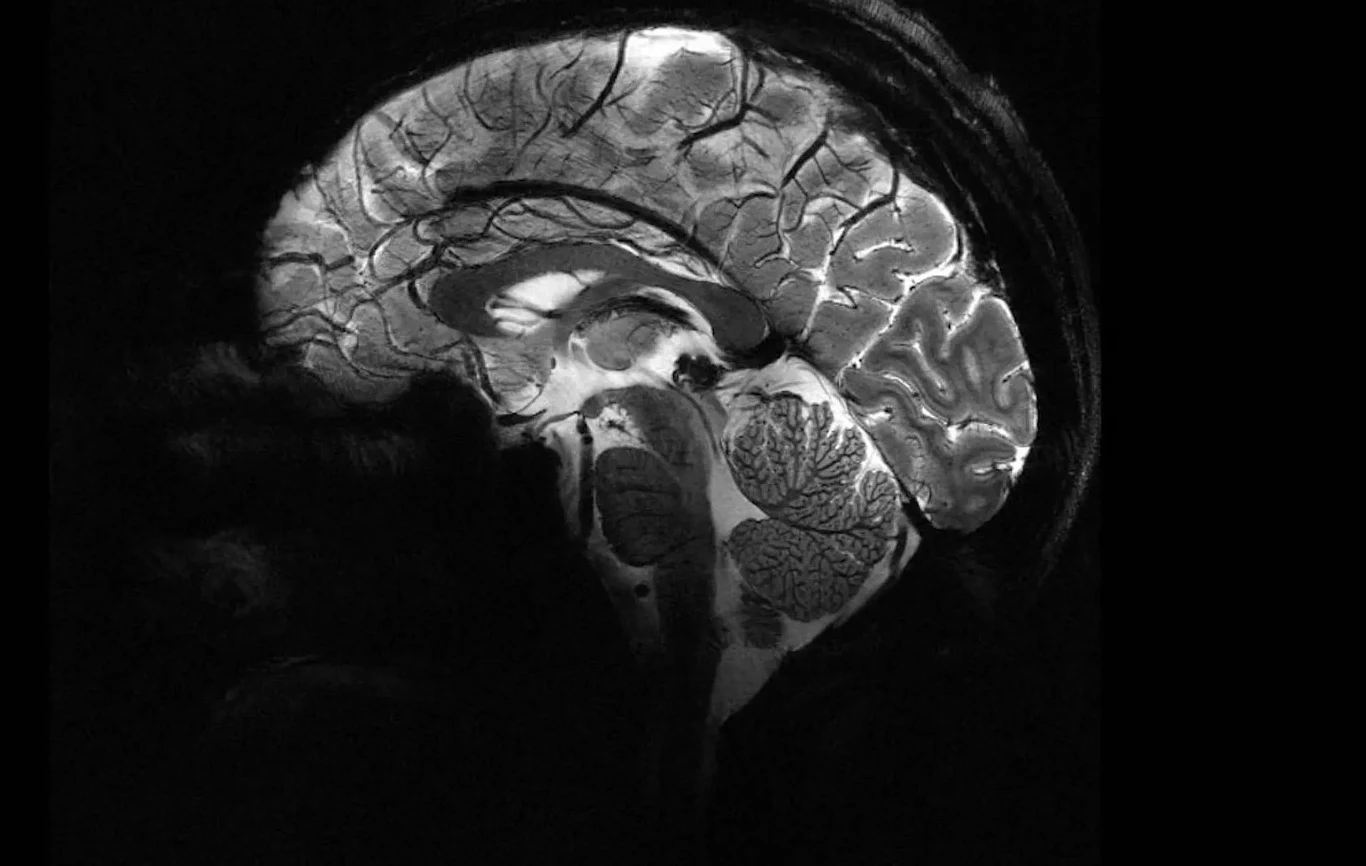

Mówiąc krótko, badacze sugerują, że nie było jednej wspólnej przyczyny objawów. Wszystkie przypadki wyjaśniono znanymi schorzeniami neurologicznymi, jak choroba Alzheimera, Parkinsona czy urazy mózgu, a część pacjentów została po prostu błędnie zdiagnozowana z powodu nieprecyzyjnych badań i nadmiernego polegania na EEG - badaniu, które łatwo źle zinterpretować.

Gdy do mediów w 2021 roku wyciekła notatka zdrowotna z Nowego Brunszwiku ostrzegająca lekarzy o rosnącej liczbie przypadków niepokojących objawów neurologicznych: demencji, halucynacji, nagłej utraty wagi czy problemów z ruchem (do momentu jej ujawnienia zidentyfikowano 48 potencjalnych pacjentów, z których kilku zmarło), w tle natychmiast pojawiła się groźba nowej choroby, przypominającej działaniem priony - białka odpowiedzialne za śmiertelne choroby neurodegeneracyjne.